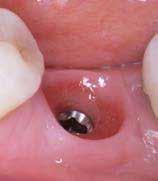

A behelyeztt implantátum primer stabilitását megfelelőnek ítéltük (kb. 40 Ncm) az azonnali terheléshez (9. kép).

Az extrakciót megelőző szituációs lenyomat alapján gyári, titán, ideiglenes abutment felhasználásával, a szék mellett készített, csavaros rögzítésű, azonnali akrilát ideiglenes koronával láttuk el, melyet 20 Ncm nyomatékkal rögzítettünk (10. kép). Az azonnali terhelés szabályainak megfelelően, az ideiglenes korona nem volt kontaktusban a szomszédos és az antagonista fogakkal.

6. kép: Implantátum-ágy preparáció. 7. a–b. képek: Implantátum behelyezés. 8. kép: A behelyezett implantátum. 10. a–b képek: Azonnali ideiglenes korona készítése. 9. kép: Megfelelő primer stabilitás.